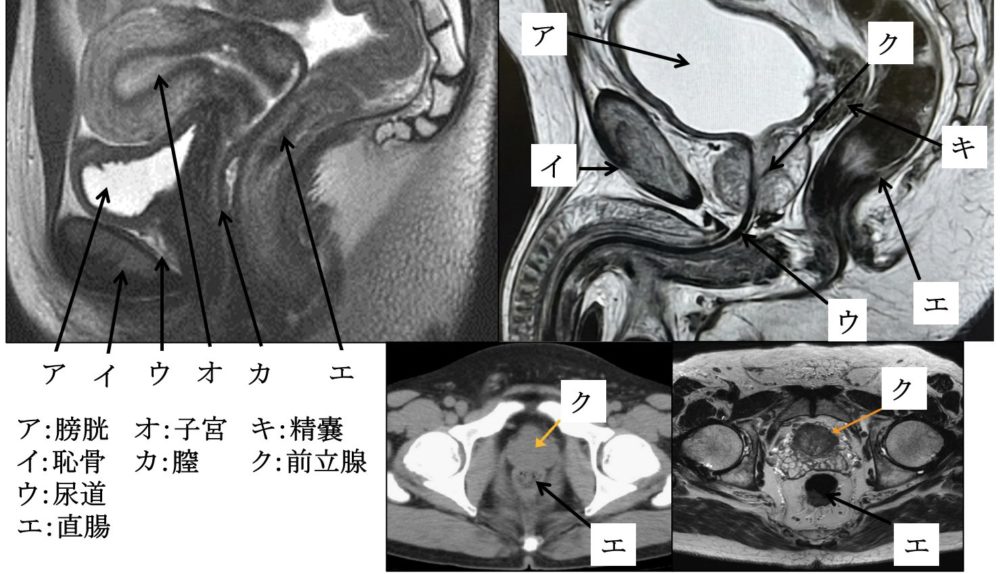

分泌腺

(71am64、62.14)

・外分泌腺

:「汗腺」「脂腺」「乳腺」

「唾液腺(顎下腺、耳下腺、舌下線)」

「肝」「膵臓」「涙腺」「前立腺」

・内分泌腺(古典的内部分泌腺)

:「下垂体」「甲状腺」「上皮小体(=副甲状腺)」

「副腎」「膵臓ランゲルハンス島」

「胸腺」「松果体」「精巣」「卵巣」

・内分泌腺(現在)

:「視床下部」「心房」「腎臓」

「消化管」「脂肪組織」